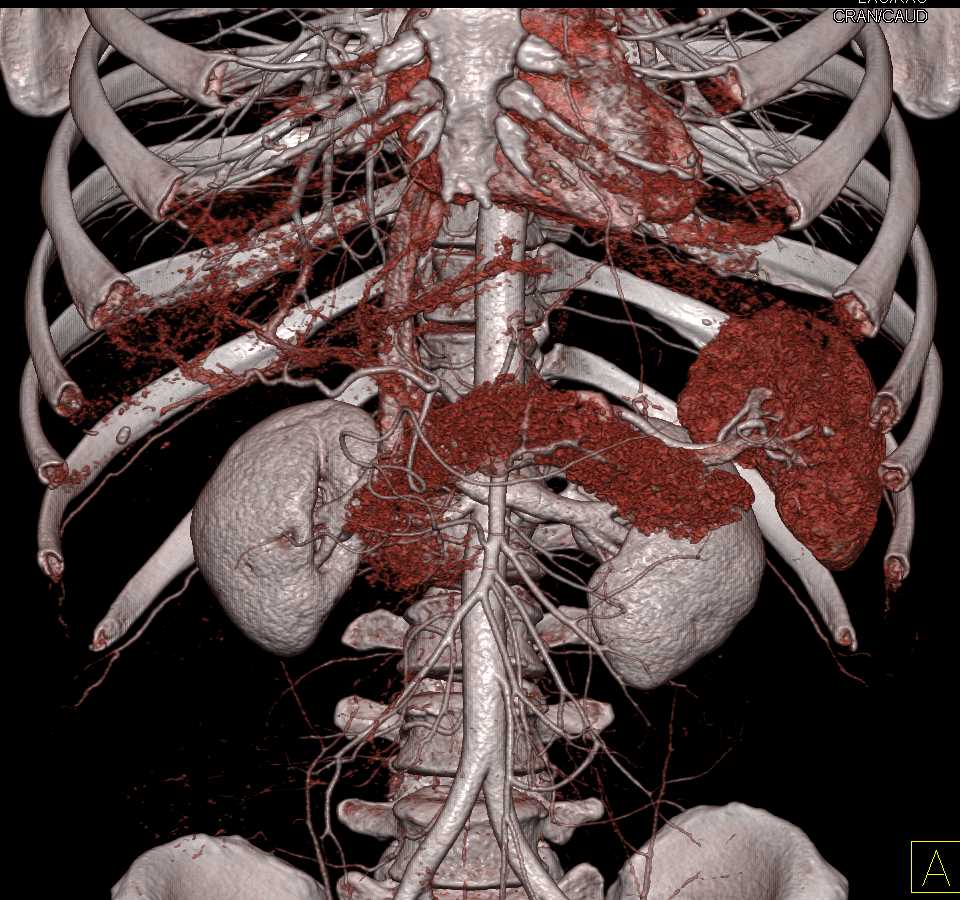

Neuroendocrine Tumor Body of Pancreas